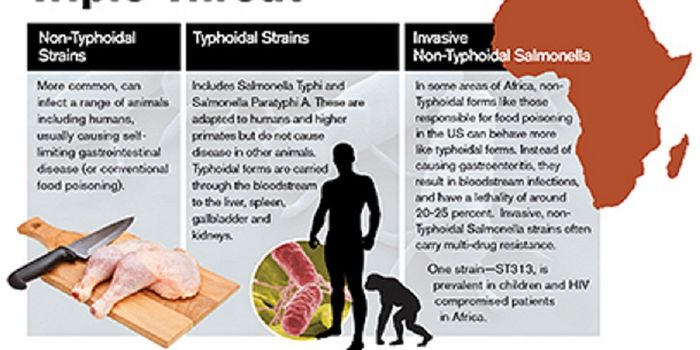

SEP 13, 2015MicrobiologySalmonella enterica are a group of rod shaped bacteria that are most commonly associated with foodborne illness in human ...

JUN 25, 2015Health & MedicineSalmonella enterica is the number one cause of bacterial foodborne illness worldwide. Infections can be transmitted by a ...

JUL 24, 2015Plants & AnimalsAccording to the CDC, non-typhoidal Salmonella causes over 1 million illnesses, 23,000 hospitalizations, 450 deaths, and ...